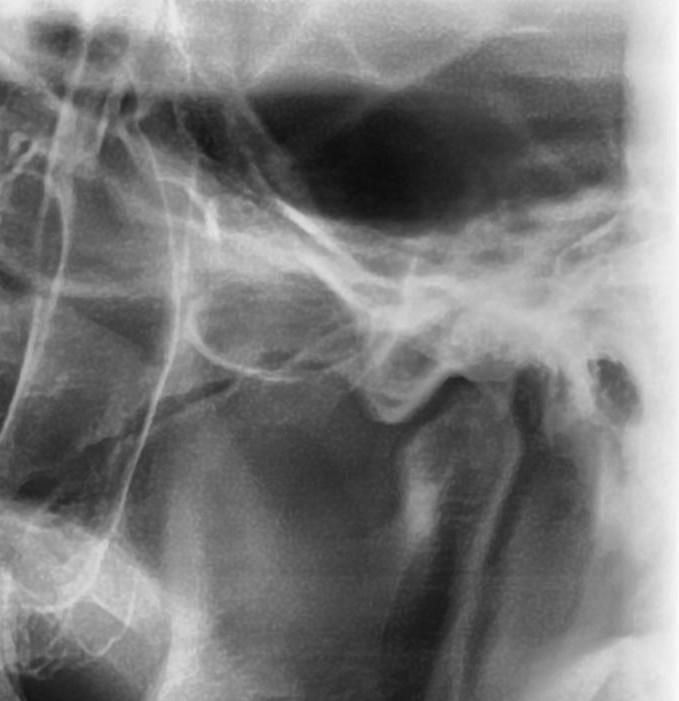

턱 관절 과두 상태 전 후 상태 한 번 봐주세요

최근에 턱 관절 통증 때문에 사진을 한 번 찍어 봤는데요 예전 사진과 비교 했을 때 어떤지 한 번 봐주시겠어요?

어떤 문제가 있는지 상세히 알려주시면 감사하겠습니다

사진1,2가 전이고 3,4가 후 입니다

• 2번 째 사진

엑스레이 상으로도 턱관절이 좋아 보이진 않습니다. 일단 구강내과를 가셔서 턱관절 정밀검사를 받아보시고 치료를 받으시는게 좋을것같습니다.

파노라마 사진으로는 턱관절을 정확하게 진단하기는 어렵습니다. 과두부분이 평평하게 되어있는 모양으로 유추해 봤을때 과두에 강한힘이 오래동안 작용했을수 있습니다. 턱관절질환은 턱관절에 가해지는 힘이 강해서 생기기 때문에 턱관절에 가해지는 힘을 줄이는것이 좋습니다.